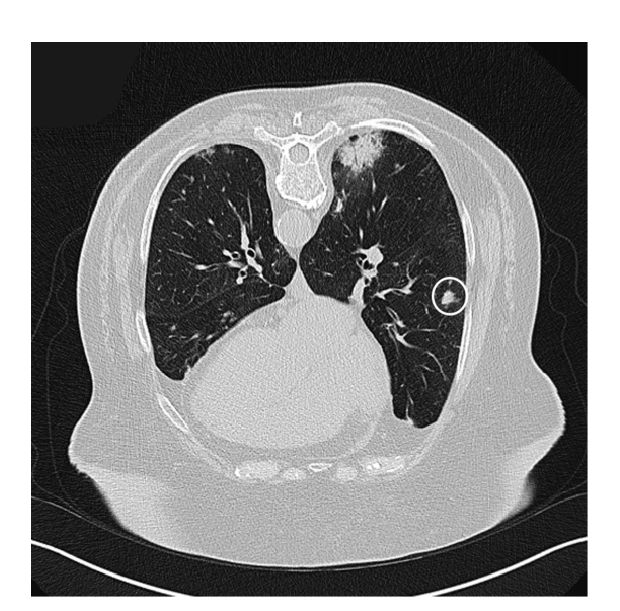

2. 影像学表现

①肺实变磨玻璃密度影;②小叶周围阴影;③环礁征;④结节或肿块;⑤小叶间隔增厚;⑥束状或条带阴影;⑦进行性纤维化。

环礁征—磨玻璃影:

图片

3. 影像学特点

(1)典型影像:斑片状肺泡浸润影(典型COP)。

(2)不常见影像:孤立性阴影(局灶性COP);浸润性阴影(浸润性COP)。

(3)少见影像:反晕轮征;进行性肺纤维化并网格及实变;多发性结节;支气管中央型实变;不规则线或带状影;小叶周围型阴影。